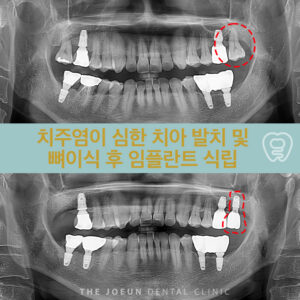

달서구임플란트잘하는곳 치조정 접근법을 통한 상악동 뼈이식술 임플란트는 치아가 빠진 부위에 티타늄으로 만들어진 인공치근을 치조골에 식립하여 상부에는 크라운을 제적하여 연결하는 보철치료르 말합니다. 치아의 뿌리부터 머리까지 자연치와 비슷한 모양으로 심미성이 뛰어나고, 자연치와 유사한 기능을 보이는데요. 이는 잇몸뼈에 식립체를 직접 식립하게 되는데 진행을 위해서는 치조골의 양과 상태가 충분해야 합니다. 치아를 상실했어도 치조골 상태가 더보기…